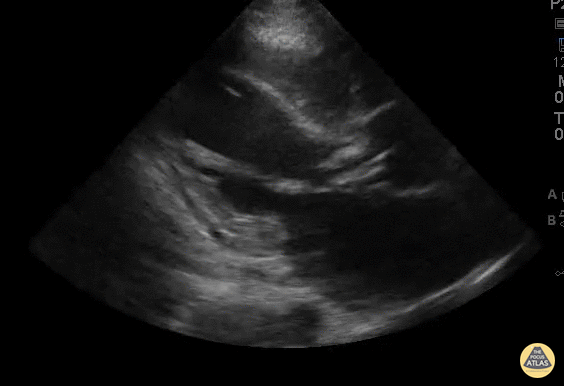

WCUME 2017 Submission for "Best POCUS" 40 year old male who presented with 1 week low grade fever and mild pedal edema and orthopnea. POCUS demonstrates a small vegetation on the anterior leaflet of the mitral valve as well as large vegetations on the aortic valve with obvious poor coaptation of valve leaflets. Dr. Peh Wee Ming - Singapore General Hospital